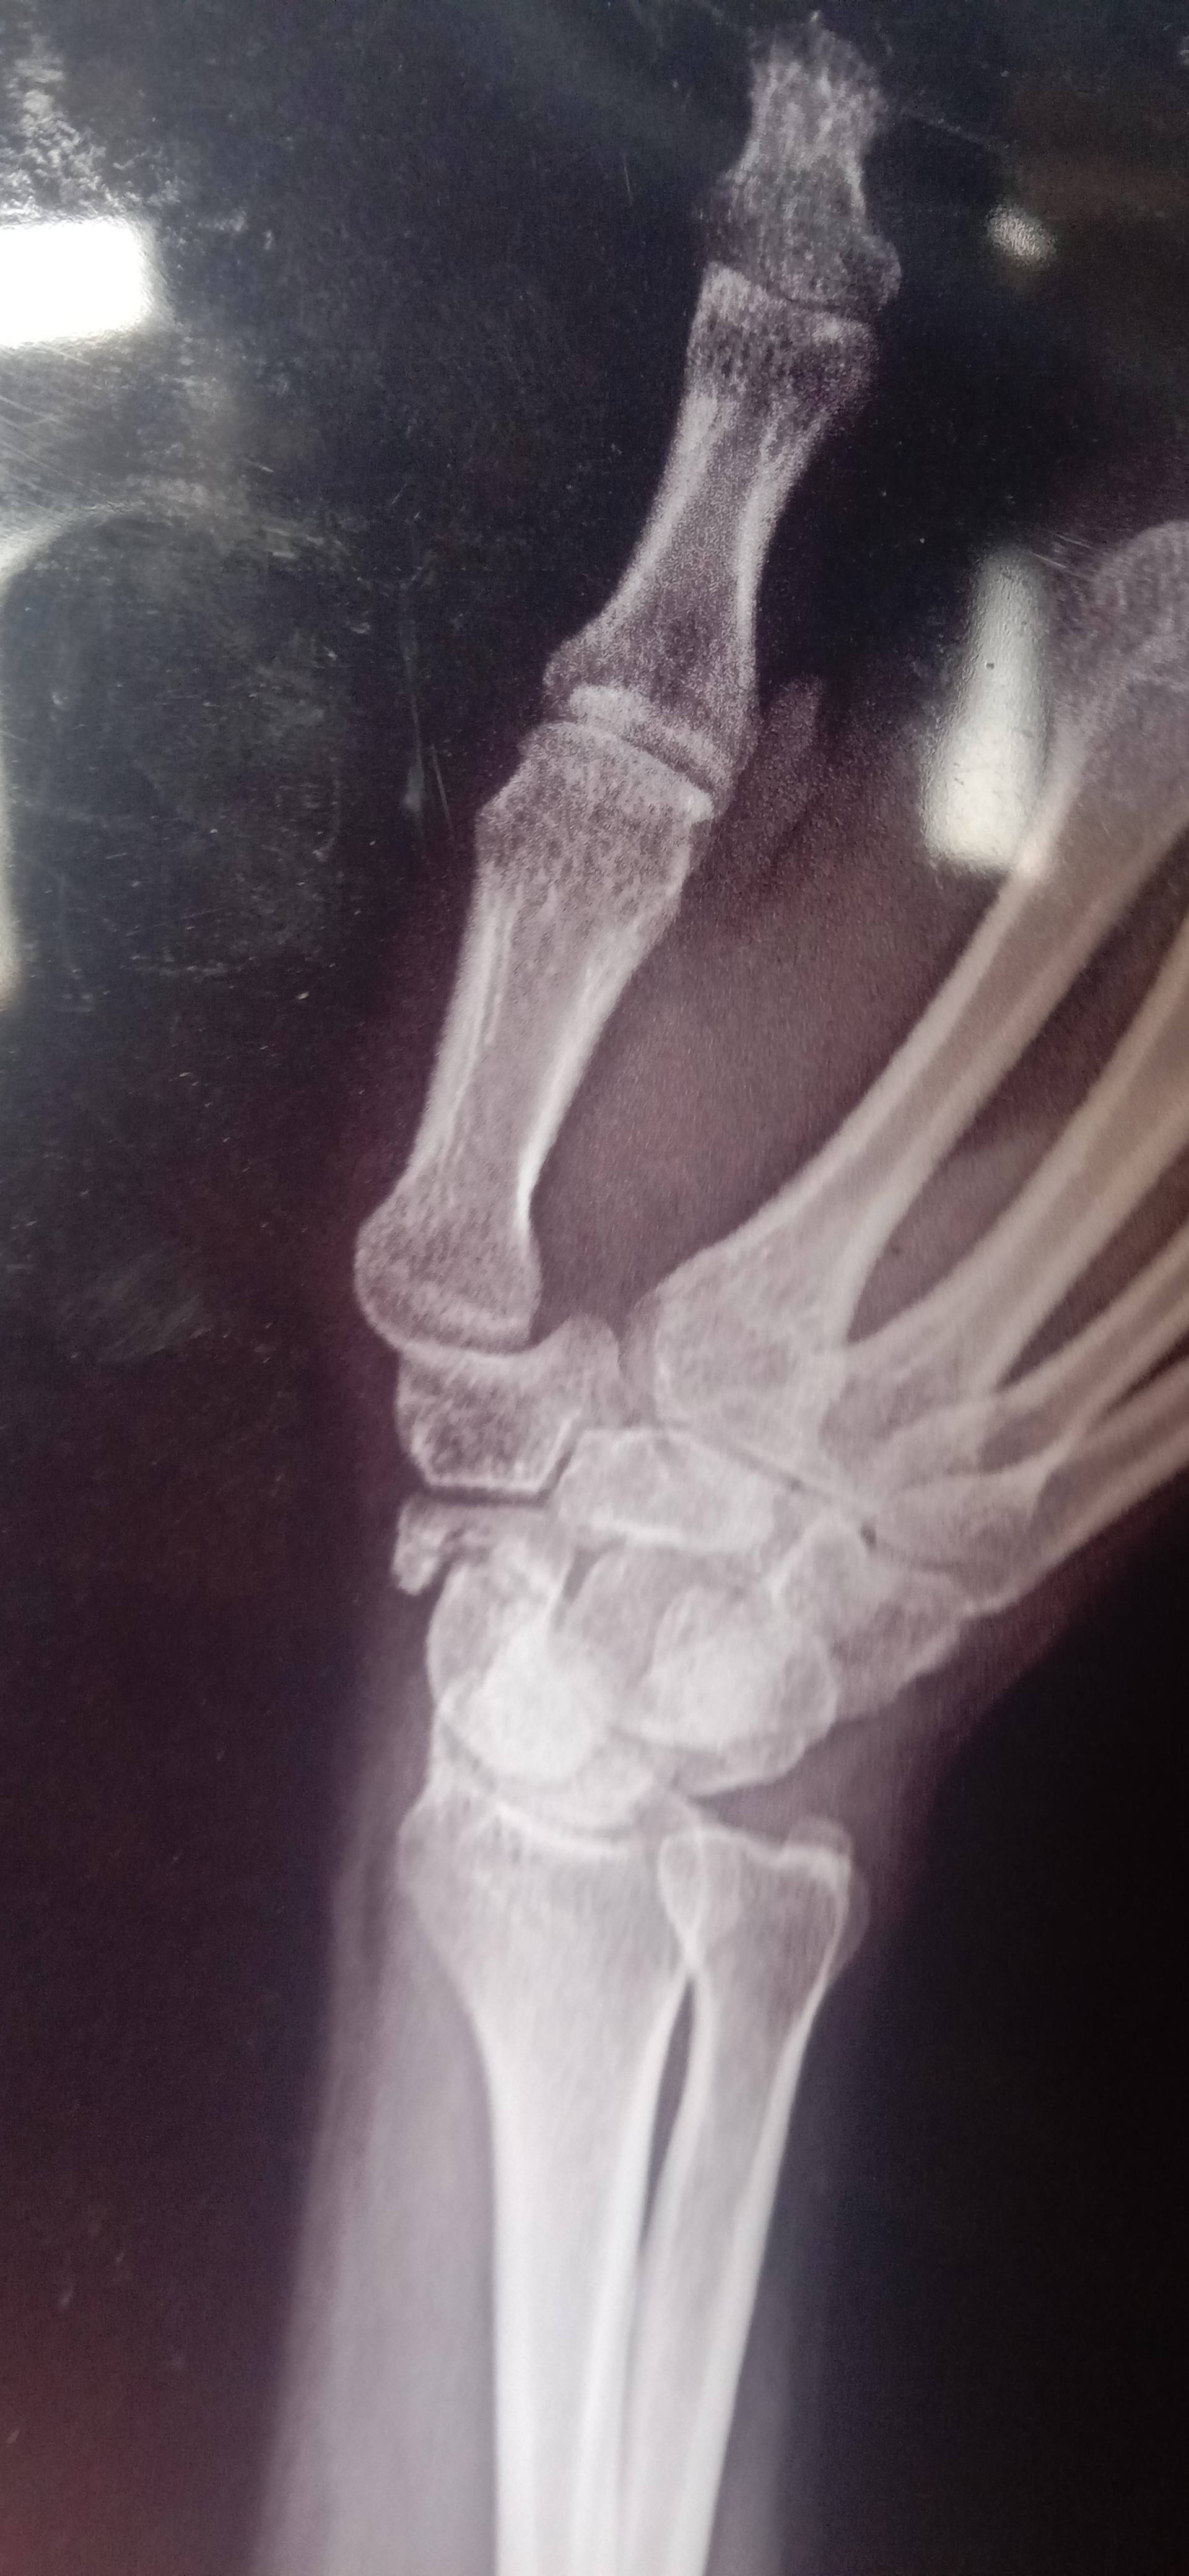

Inder